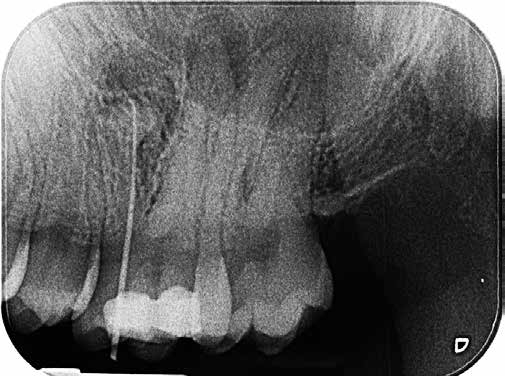

Bei der Diagnose des schmerzfreien Patienten stellte sich die beschriebene Erhebung schließlich als Fistel heraus (Abb. 1). Der Zahn 26 sowie die Nachbarzähne wurden zunächst einer Sensibilitätsprüfung unterzogen, wobei der Kältetest an Zahn 26 negativ ausfiel. Im Anschluss erfolgte dann die Anfertigung der diagnostischen Röntgenaufnahmen (Abb. 2 und 3). Dazu wurde ein Guttapercha-Stift in den Fistelgang eingebracht, um die Lokalisation der Entzündung zu erleichtern. Speziell bei der distal exzentrischen Aufnahme ließ sich dabei an 2 Wurzelspitzen des Zahns 26 die Entzündung ausmachen (Abb. 2). Insofern war in diesem Fall eine endodontische Behandlung des Zahnes angezeigt. Für diese wurde sogleich ein Folgetermin vereinbart.